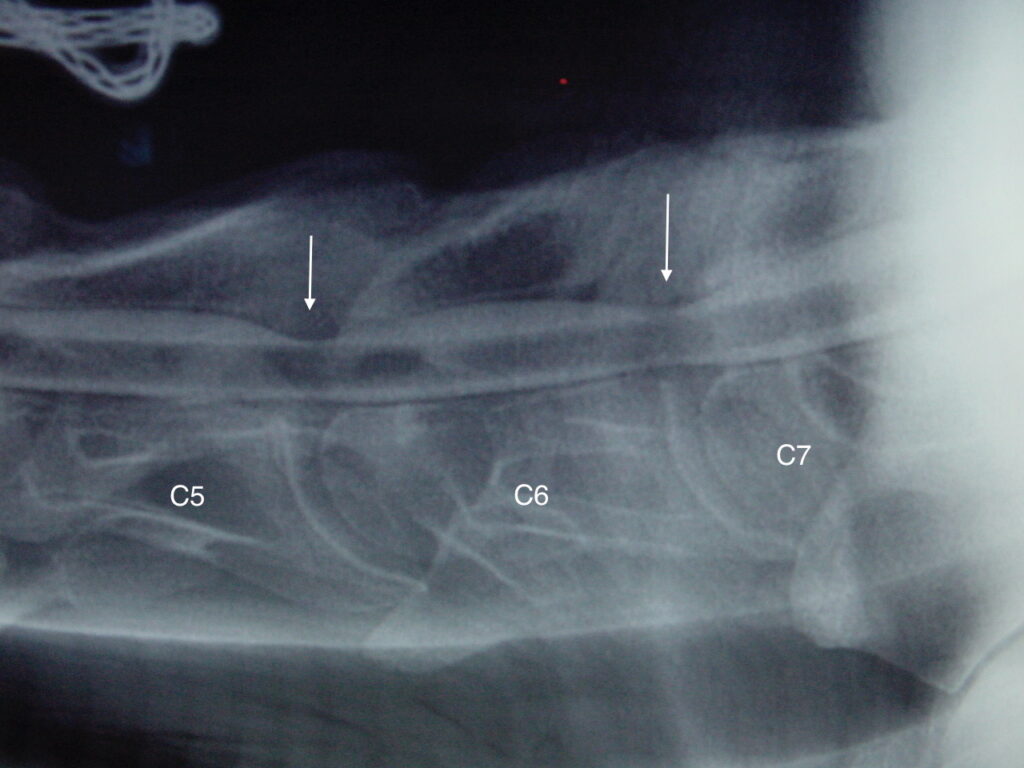

Obrázek 2a, b: Hříbě s ataxií a horečkou způsobenou zánětem kostí obratlů C6–C7. Na CT je jasně patrné výrazné poškození kostí v důsledku infekce (bílé šipky). Na obrázku 2b je stejný případ z jiného pohledu

Obrázek 2c: Postižená kost a meziobratlová ploténka byly chirurgicky odstraněny a oba obratle byly spojeny pomocí ploténky a šroubů